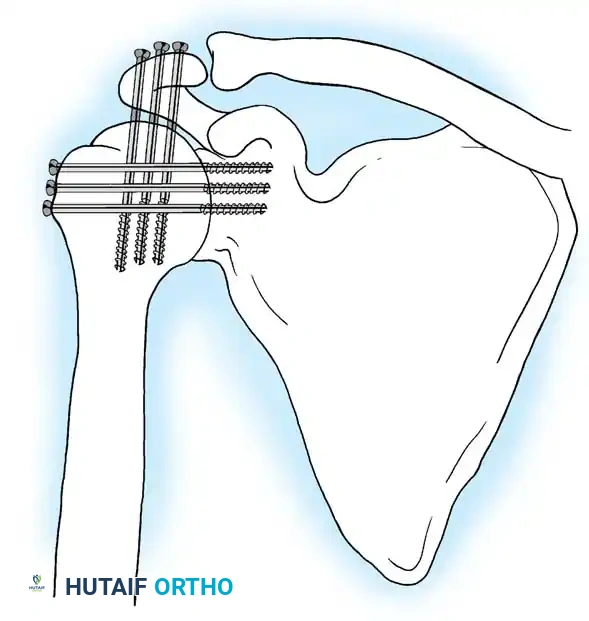

5. Rigid Internal Fixation

The most robust biomechanical construct involves a heavy, malleable plate (such as a 10- to 14-hole 4.5mm pelvic reconstruction plate or a dynamic compression plate). The plate is meticulously contoured to lie flat along the spine of the scapula, bend over the acromion, and extend down the lateral shaft of the humerus.

Screws are placed sequentially:

1. Scapular Spine: Cortical screws are placed into the dense bone of the scapular spine.

2. Acromiohumeral Fixation: Screws are passed through the plate, across the acromion, and into the humeral head.

3. Glenohumeral Fixation: Long, fully threaded cortical or cancellous screws are directed through the plate, through the humeral head, and deep into the glenoid neck and vault. This is the most critical step for achieving compression across the primary fusion site.

4. Humeral Shaft: The distal portion of the plate is secured to the humeral diaphysis.

If additional stability is required, or if bone quality is poor, a second plate (double plating technique) can be applied posteriorly.

Radiographic confirmation of a contoured reconstruction plate achieving rigid acromiohumeral and glenohumeral compression.